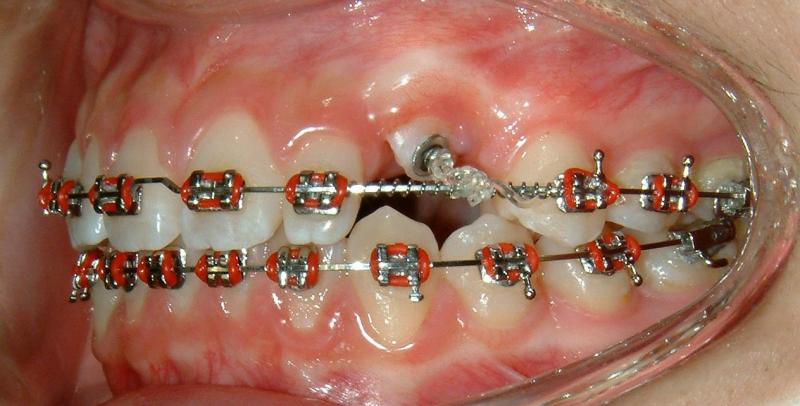

Fig. 11 Forced eruption, 8 months after surgical exposure (progress)

© Copyright 2007-2014, Vu Orthodontics. All rights reserved.